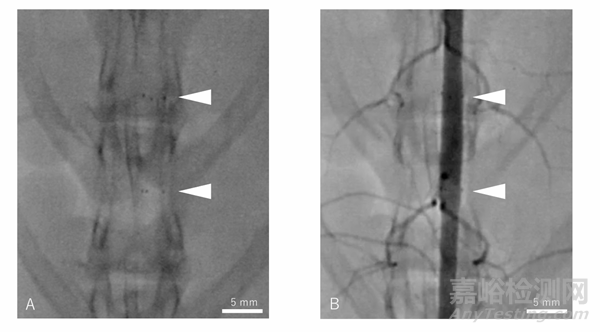

補(bǔ)充圖2:PLLA涂層MgBRFD植入后3個月的血管造影。A:透視圖像。顯示支架本身不具顯影性,僅在兩端有顯影標(biāo)記。B:血管造影圖像。顯示主動脈及其側(cè)支的通暢性,支架覆蓋在這些血管上。白色箭頭:指示顯影標(biāo)記的位置。